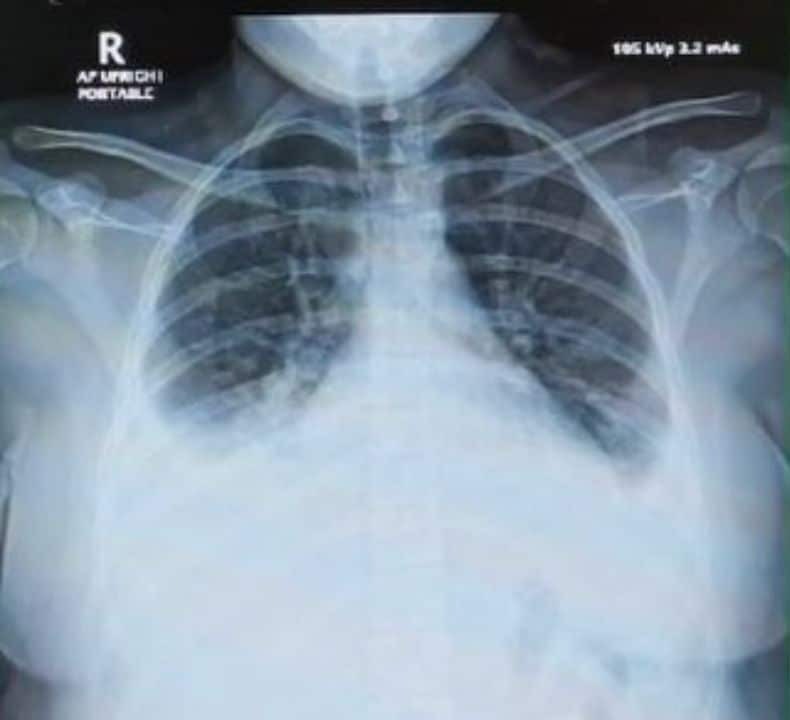

ထိုသူသည် နာတာရှည်ရောဂါမရှိ၊ ဆေးလိပ်သောက်လေ့မရှိဘဲ ပြင်းထန်သောအဆုတ်ရောင်ဝေဒနာ ခံစားခဲ့ရသဖြင့် အောက်ဆီဂျင်ပမာဏ (high-flow oxygen) မြင့်မားစွာပေးခဲ့ရပြီး၊ ပိုးသတ်ဆေးနှင့် စတီးရွိုက် (steroids) များဖြင့် ကုသခဲ့ရသည်။

လက်ရှိတွင် လူနာသည် ပြန်လည်သက်သာလာပြီဖြစ်သော်လည်း ဆက်လက်စစ်ဆေးချက်များအရ သွေးဖြူဥတစ်မျိုးဖြစ်သော eosinophils များ မြင့်တက်နေပြီး ၎င်းသည် ရုတ်တရက် အဆုတ်ရောင်ခြင်း (acute eosinophilic pneumonia) ဖြစ်ပြီး၊ အချိန်တိုအတွင်း အဆိပ်ငွေ့အမြောက်အမြား ရှူရှိုက်မိခြင်းကြောင့် ဖြစ်နိုင်ခြေအလွန်များကြောင်း၊ အထူးသဖြင့် ဆေးလိပ်ပုံမှန်မသောက်သူများတွင် ဖြစ်လေ့ရှိကြောင်း ဆရာဝန်က ရှင်းပြသည်။

အလားတူ လွန်ခဲ့သည့် ၅-၆ နှစ်ခန့်တည်းက တစ်နှစ်လျှင် တစ်ကြိမ် သို့မဟုတ် နှစ်ကြိမ် အဆုတ်ဆေးခြင်းပြုလုပ်ရန် လိုအပ်သည့်လူနာတစ်ဦးမှာ နောက်ဆုံးအကြိမ်အဆုတ်ဆေးပြီး ၂ လမပြည့်မီအချိန်တွင်း အသက်ရှူလမ်းကြောင်း ပျက်စီးကာ အသက်ရှူပိုက်ထည့်ရန် လိုအပ်သည့်အခြေအနေဖြင့် ဆေးရုံသို့ ပြန်လည် ရောက်ရှိလာကြောင်း ဖော်ပြထားသည်။

၎င်းသည် နှစ်ကာလရှည်စွာ PM2.5 နှင့် လေထုညစ်ညမ်းမှုဒဏ် ခံခဲ့ရမှုကြောင့် အဆုတ်အတွင်း ပရိုတင်းဓာတ် ပုံမှန် မဟုတ်သည့် အခြေအနေရှိသည့် လူနာတစ်ဦးဖြစ်သည်။ ကုသမှုပြုလုပ်နေသည့်အချိန်အတွင်း ထွက်လာသော အရည်များမှာ သွေးများပါဝင်လာသည့်အတွက် ယခင်ထက်ပို၍ အဆုတ်ယောင်ရမ်းနေသည်ကို ဖော်ပြနေကြောင်း ဆရာဝန်က ဆိုသည်။

ယခုဖြစ်စဉ်တွင် အဆုတ်အတွင်း သွေးယိုစီးမှုများပြားခြင်းနှင့် အသက်ရှူပြွန်အတွင်း ချွဲသလိပ်များ များပြားလာခြင်းက အဆုတ်ဒဏ်ရာရရှိမှု ပိုမိုပြင်းထန်ကြောင်း ပြသနေသည်။